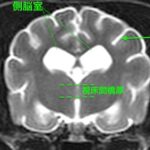

10歳、去勢雄の猫ちゃんで、 1年前からてんかん発作が続いているとのことでした。発作は抗てんかん薬などの内科治療ではコントロールできず、週3~4回発現していると…